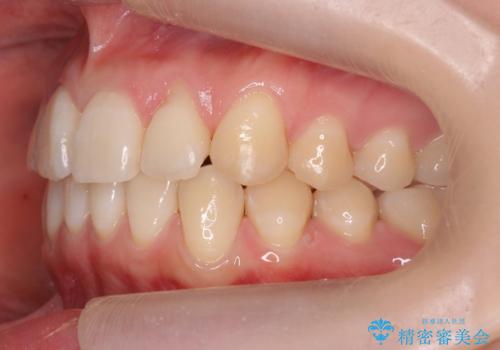

前歯がねじれている 奥歯を後ろに下げて歯を抜かずに並べました

- 前歯のねじれを主訴に来院。

前から2番目の歯がねじれて下の歯の内側に入っていました。

また、奥歯のかみ合わせが上の奥歯が若干前に並んでおり、それで前歯が入りきらずにねじれていました。

歯を抜かずに奥歯を後ろに下げてマウスピースで矯正しています。

上の奥歯を後ろに下げて前歯のねじれを治すスペースを確保しました。

奥歯を後ろに下げるために、矯正用インプラントを使用しています。